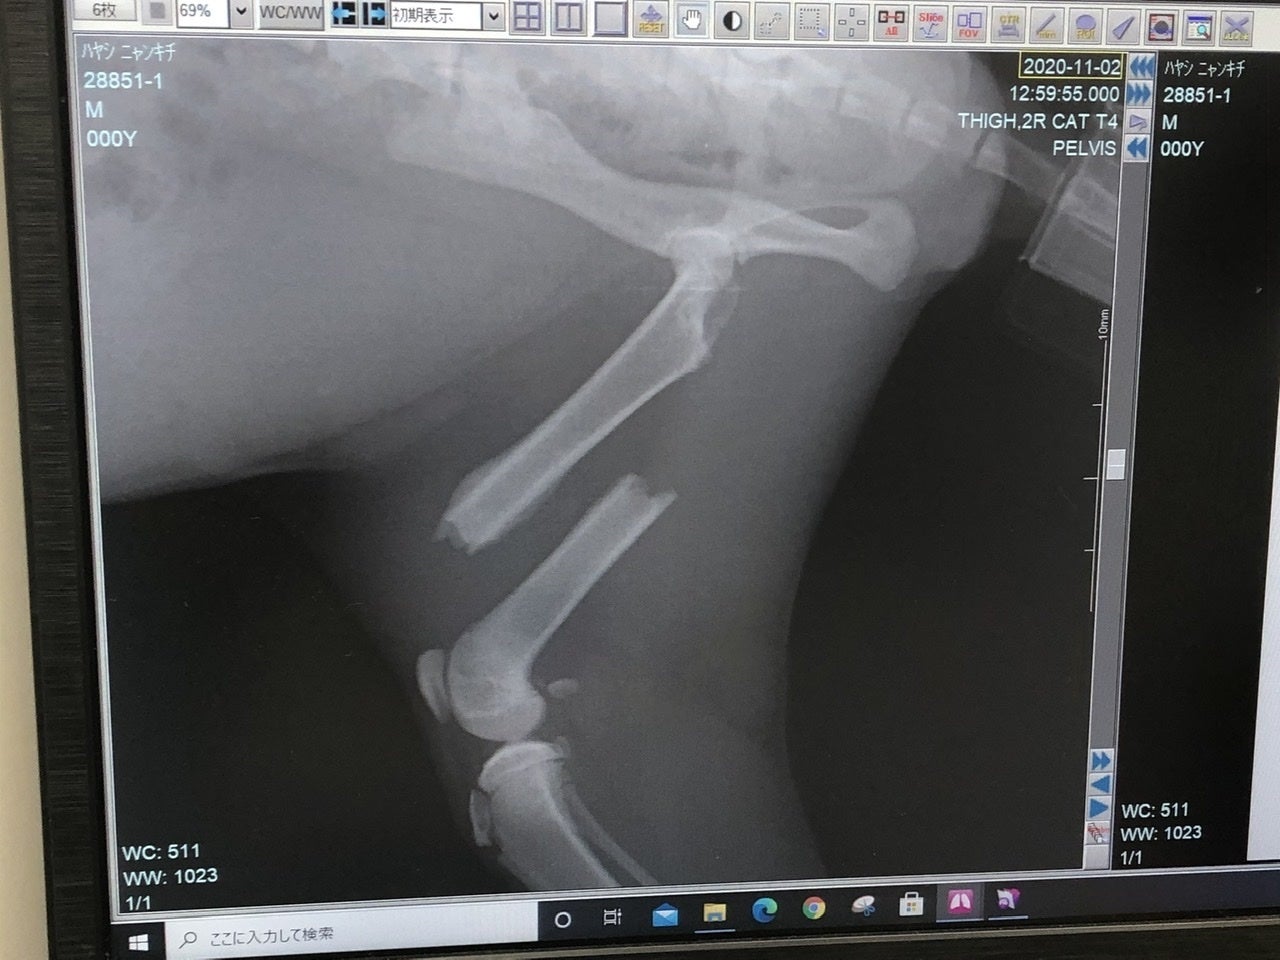

「右上腕部末端(肘)骨折」

「右後ろ大腿骨(付根)骨折」

の2箇所が骨折していました。

それ以外のキズや臓器系、病気などは無く、強い衝撃が生後間もなく右半分に当たり、骨折したものだと、先生がおっしゃられていました。

「右後ろ大腿骨(付根)」は肉を剥がして奥まで入った骨を戻し、固定の金具をつけます。

次に金具を入れて固定した画像。The 骨折画像と比べると、本当に綺麗に固定されていました。でもまあ、よくこんな折れた状態で店まで、歩いてきたなと。